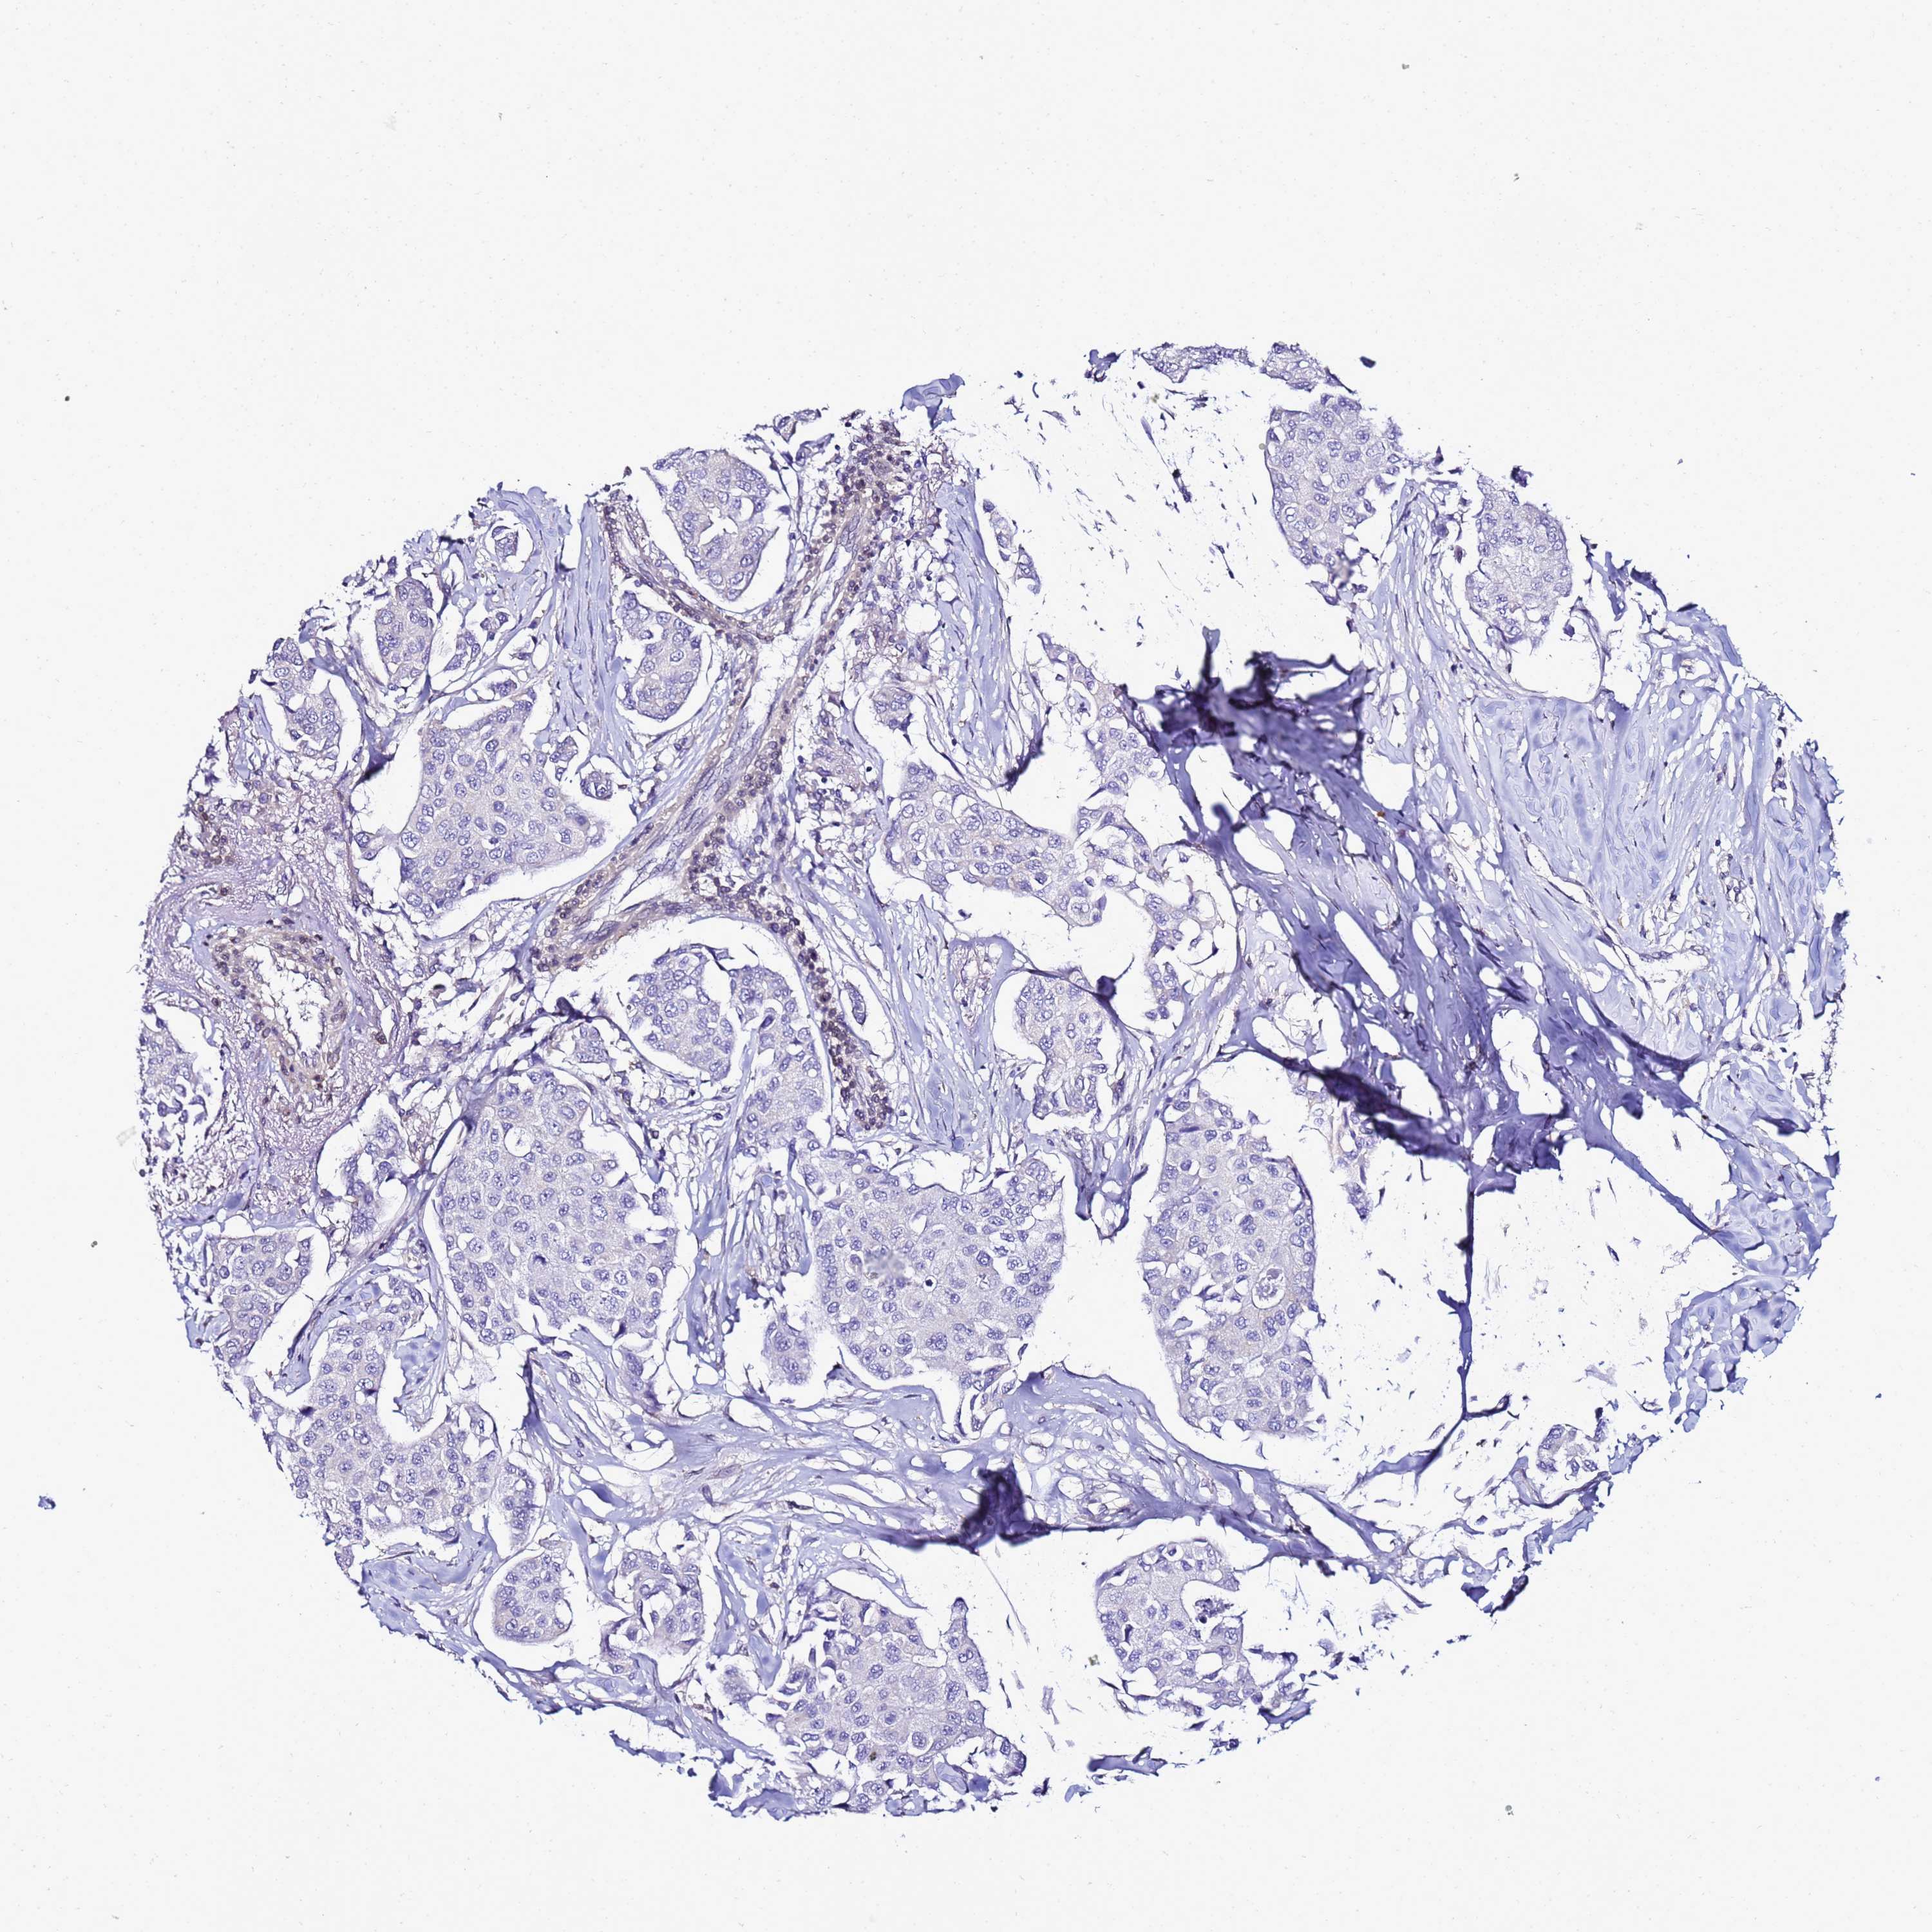

BRCA TCGA BRCA VALIDATION PROTEIN EXPRESSION